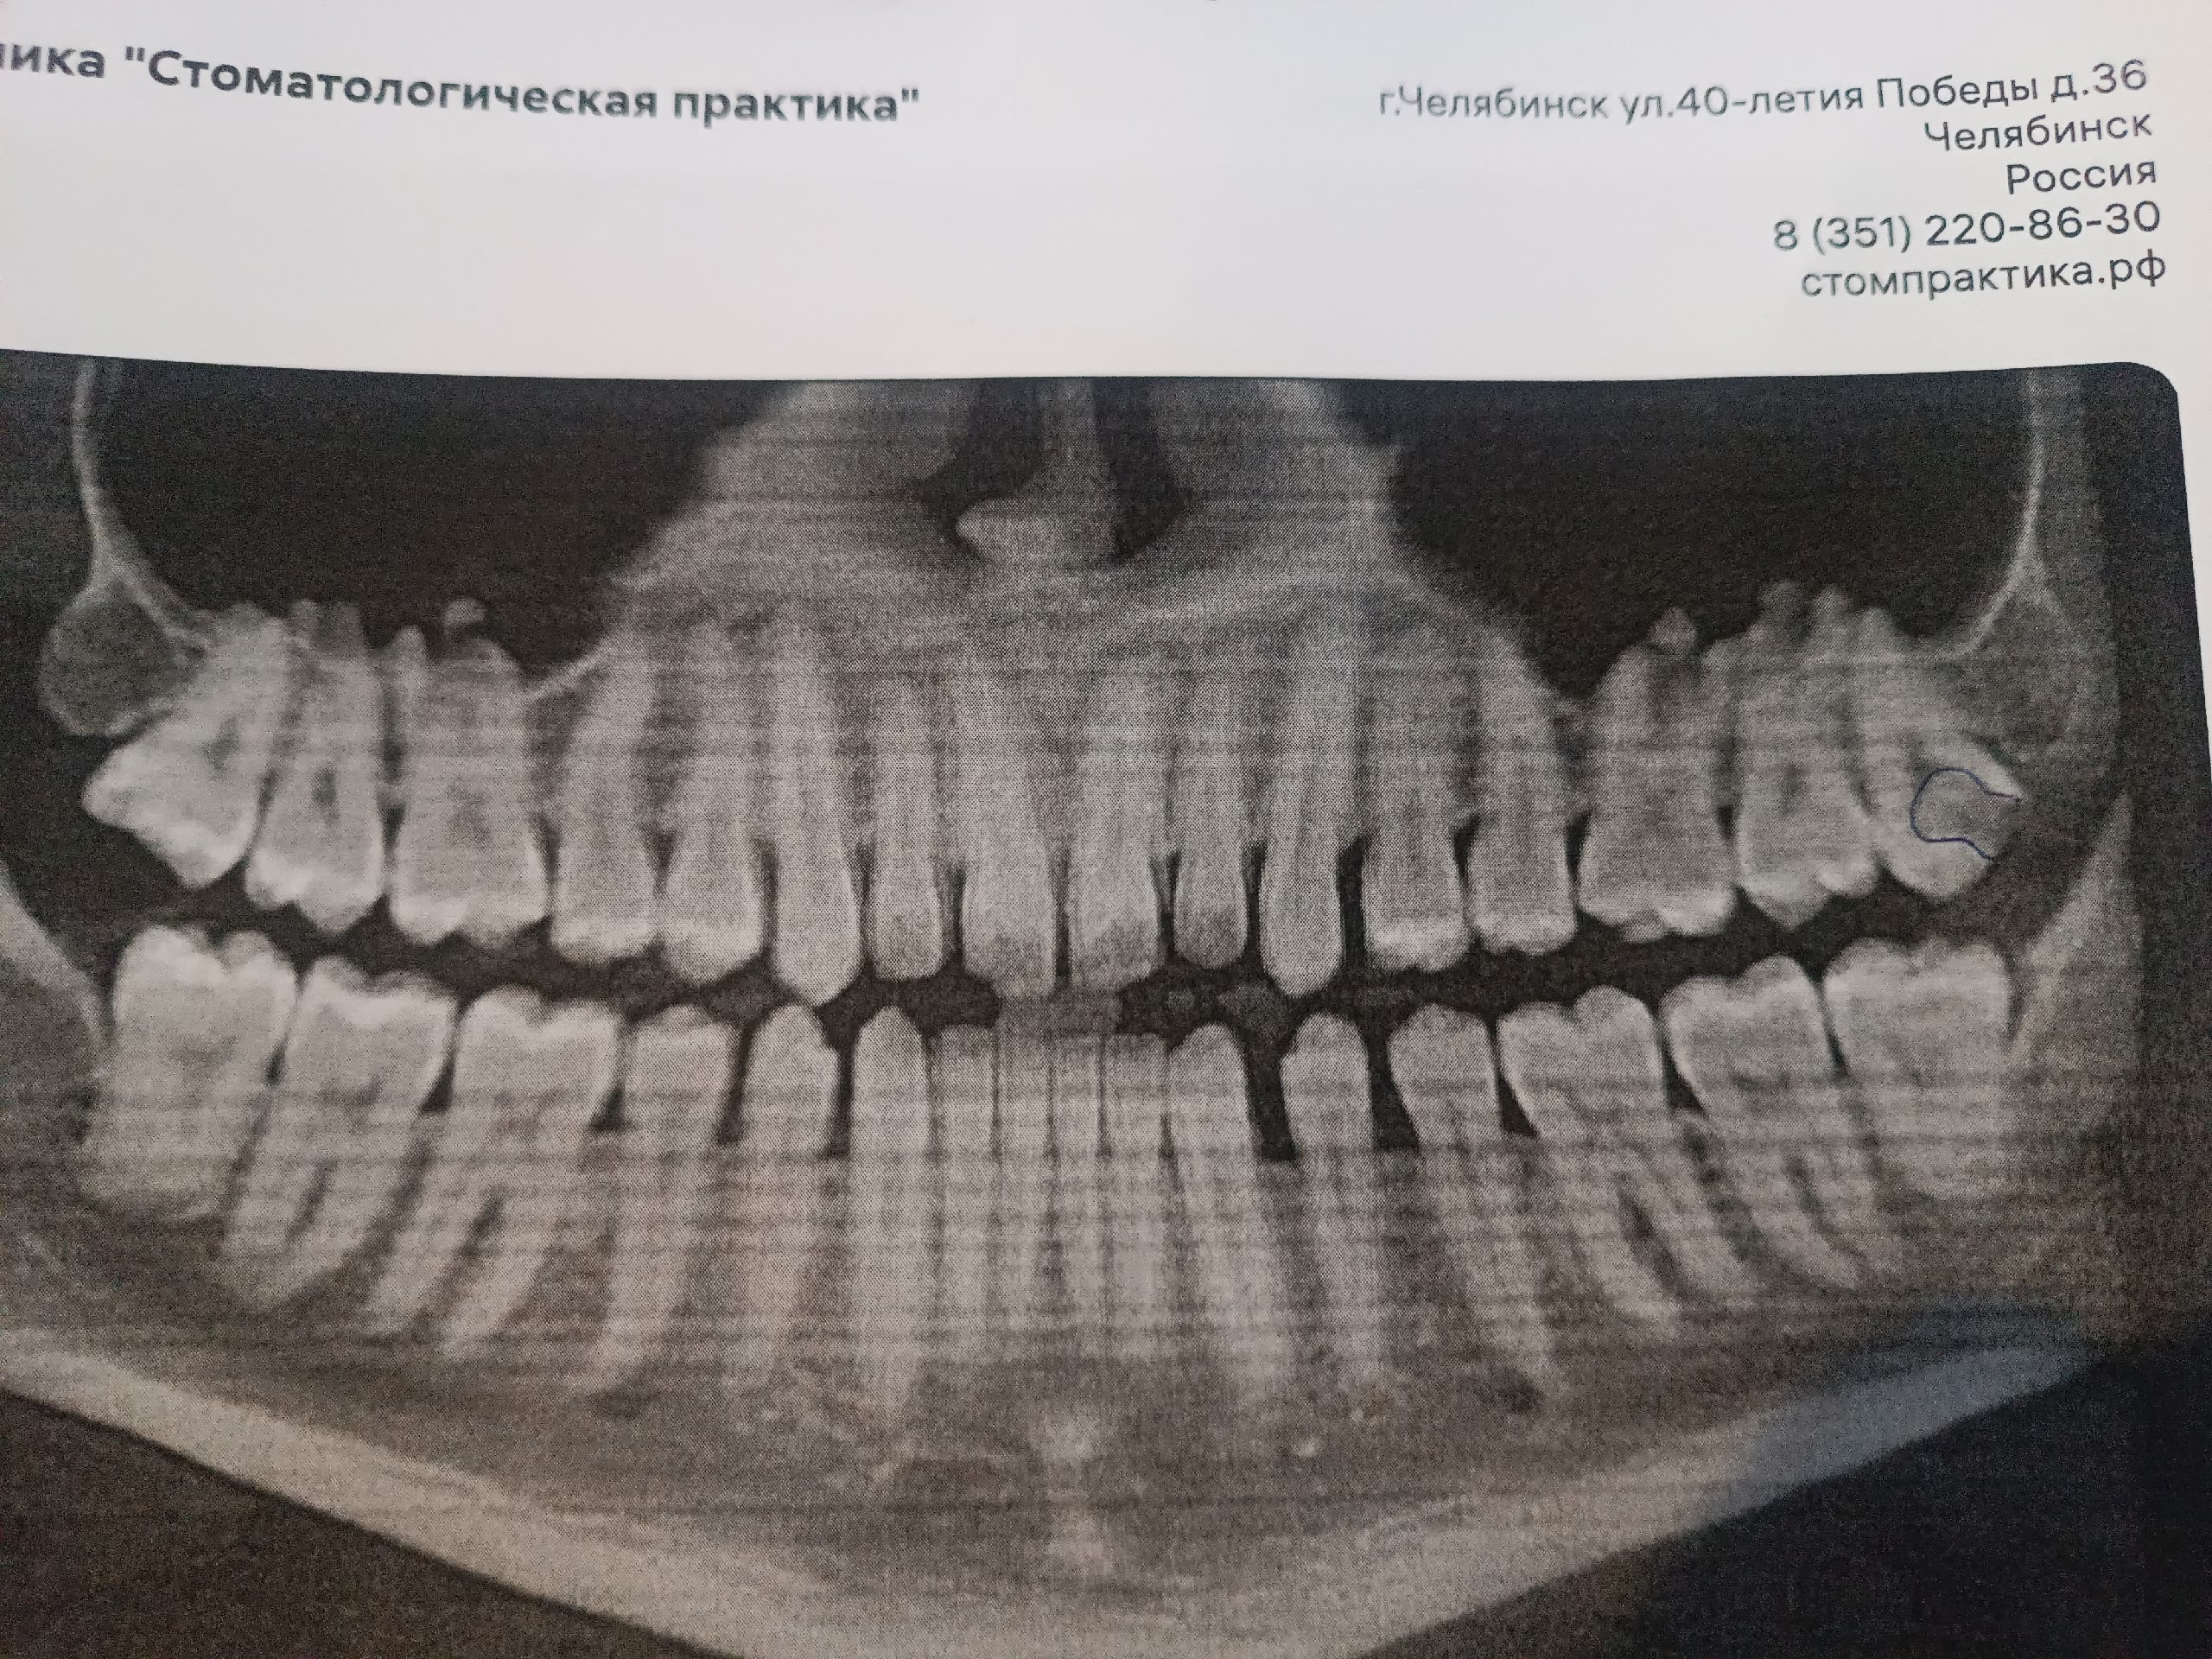

Аноны, добрый вечер.

Посоветуйте пасту зубную после пломбирования и чистки от камня передних зубов.

Спасибо.

Аноним 06/08/25 Срд 05:38:29 1634925 25

Ска, весь рот в гное, будто бы стоматит, сходил к зубным феям - сказали все збс с корнями зубов и ни одного намёка на кариес где-либо, хотя начиналось всё будто бы флюс и самый пиздец около одного зуба, прописали онли антибиотики, но самое очко , что болезненность ещё и в области мягких тканей подбородка, который и отдает в этот самый пиздец при надавливании - даже будто бы второй подбородок чуть-чуть присутствует, температура и общая слабость, есть риск флегмоны? пиздец за шо(

Аноним 06/08/25 Срд 10:08:53 1634947 26

Как профиль лица меняется после удаления восьмерок? В инете нашел только фотки до/после у женщин, и вроде как челюга уменьшается. У мужиков так же? После удаления не получится больше моггать челюхой омежек?

Аноним 07/08/25 Чтв 13:36:06 1635134 27

>>1634947

>Как профиль лица меняется после удаления восьмерок